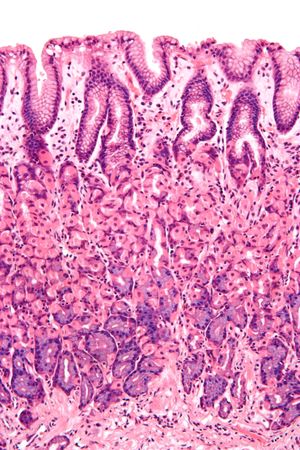

의 점막 이미지로, 원주형 세포로 구성된 상피(상단, 길쭉한 구멍을 향하고 있음)를 보여준다.

점막의 상피 내벽은 위장관에 따라 다르다.[1] 상피는 여러 층의 세포로 구성되어 있으면 중층, 한 층의 세포로 구성되어 있으면 단층이라고 한다. 세포의 모양은 기둥 모양이면 원주형, 편평하면 편평형이라고 부른다.

• 에서 상피는 단층 원주형이며 분비를 처리하기 위해 위소와와 샘으로 구성되어 있다.[1]

• 소장에서 상피는 흡수를 위해 특화된 단층 원주형이다. 원형 주름과 융모로 구성되어 있으며, 장세포에는 미세 융모가 있다. 미세 융모는 흡수 면적을 증가시키는 가장자리 띠를 형성한다. 회장에는 때때로 고유층에 페이어판이 있다. 브루너샘은 십이지장에서 발견되지만 소장의 다른 부분에서는 발견되지 않는다.[1]

• 잘록창자에서 상피는 단층 원주형이며 융모가 없다. 점액을 분비하는 술잔 세포도 존재한다.[1]